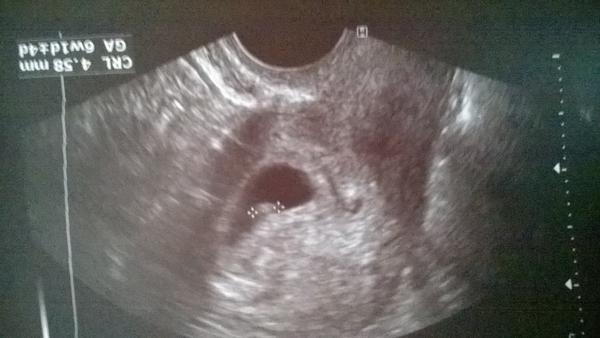

Těhotenský test. Dávám fotku. Co myslíte?